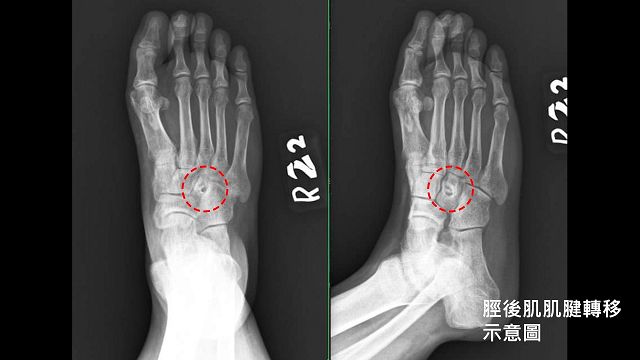

第2階段由楊鎮源醫師施以神經鬆解手術,將受傷的坐骨神經與周圍嚴重沾黏的纖維化組織仔細分開,達到神經減壓目的,緩和右腳持續電麻感。最後進行肌腱轉移手術,將脛後肌肌腱繞道固定至足背骨頭,加強腳掌背屈的力量,改善垂足。階段性的關節重建、神經鬆解、肌腱轉移手術,有效地改善了病人的麻痛感,恢復走路能力可自理生活,目前只要定期回診即可。